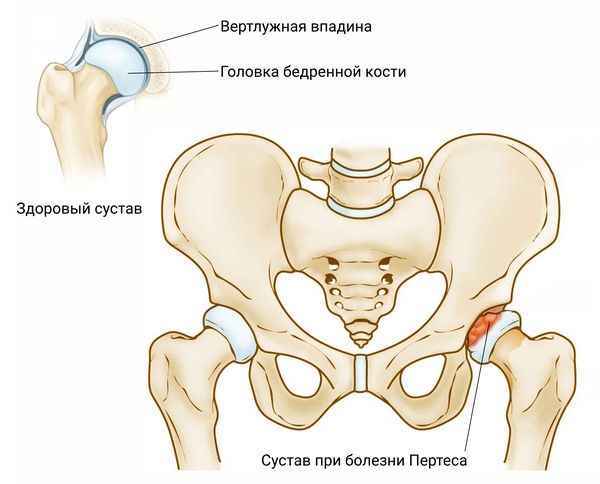

Оссификация тазобедренных суставов: что это и как проявляется?